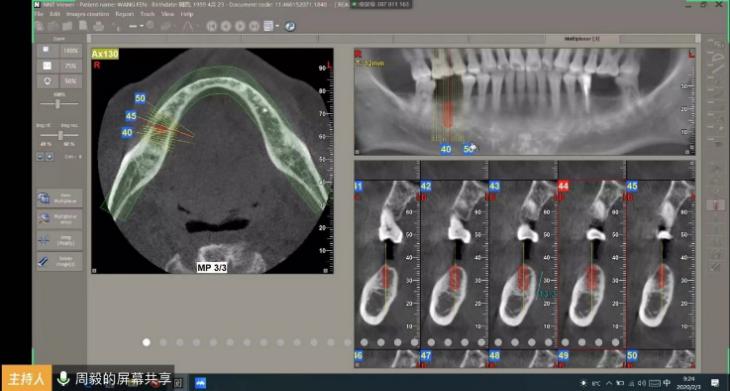

新年第一次晨课由修复科的周毅老师主讲,周老师不仅为学生讲解怎么拍摄用于种植修复的CBCT,还从病例入手,通过NNT软件线上实操模拟了种植体植入的过程。原定半小时的课程内容,在修复科老师和115多位规培学员一起热情参与、积极讨论下持续了一小时。